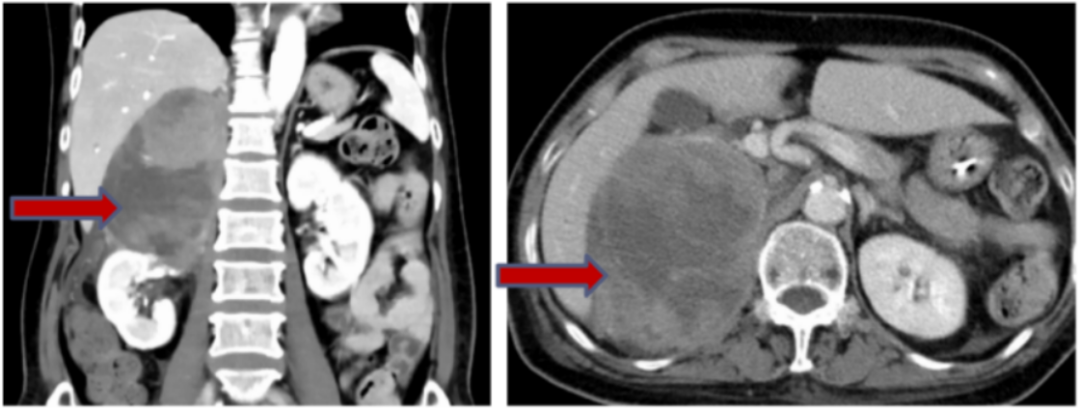

胸腹增强CT(2025-4-8):双肺散在多发炎性病变,双肺局部膨胀不全,双侧少量胸腔积液;腹膜后巨大占位(76×101×124mm),性质、来源待定。

图4 患者胸腹CT表现

2025-03-03顺利完成淋巴细胞采集,2025-03-04腹部B超示:肝内可见密布多个大小不等的低回声结节,较大者约46×38mm(右叶)。

自2025-03-04起,予匹妥布替尼200mg qd单药治疗。2025-3-12复查腹部B超:肝内可见密布多个大小不等的低回声结节,较大者约35×26mm(右叶)较2025-03-03肿瘤缩小近50%,且患者无药物相关不良事件,疗效尚可。